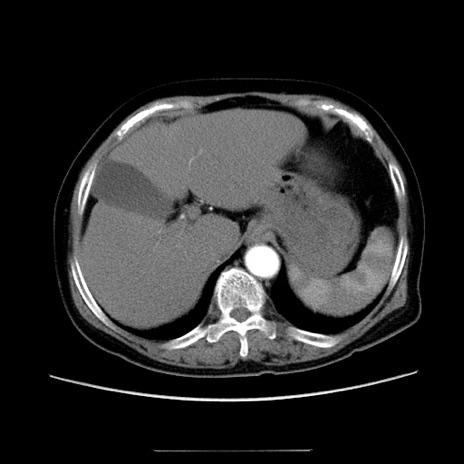

症例5(横断像)

【症例】70歳代女性

【主訴】お腹が張る

【現病歴】1週間くらい前から腹部膨満の自覚あり。昨日夜から増悪したため、本日救急外来受診。

【身体所見】意識清明、BT 36.5℃、BP 165/106mmHg、HR 80bpm、SpO2 98%、腹部:膨満、軟、自発痛・圧痛なし、触診にて不快感あり、腸蠕動音:減弱

【データ】WBC 12600、CRP 1.04